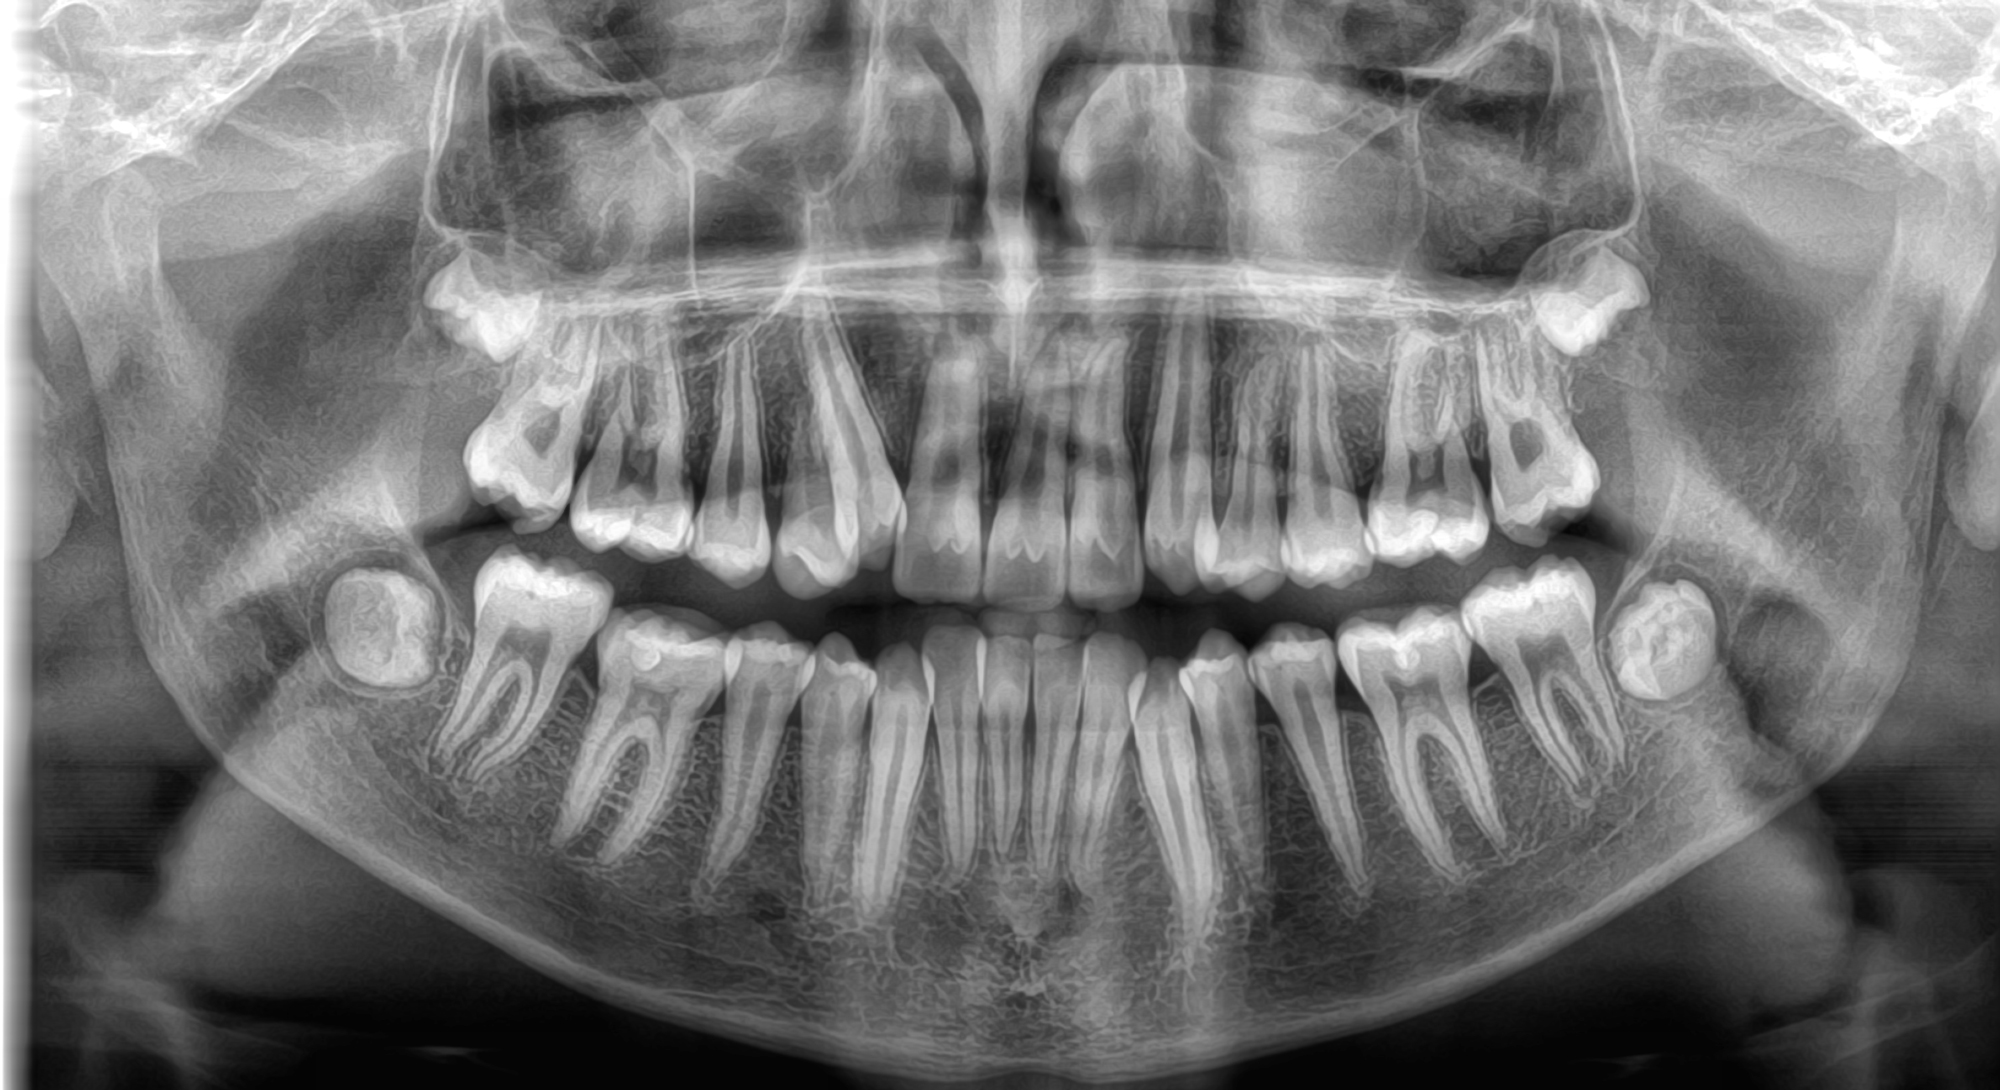

Το νέο μοντέλο CS 8200 3D Neo Edition της Carestream Dental συνδυάζει Ψηφιακή Πανοραμική με Ογκομετρικό Τομογράφο CBCT, με επιλογή εννέα οπτικών πεδίων και ανάλυση έως 75μm.

Με νέο εύχρηστο λογισμικό και ακόμα μεγαλύτερες δυνατότητες όπως το CS MAR, αλγόριθμος NAR, ανατομικά φίλτρα Endo, Perio,τεχνολογία Tomosharp, το καθιστούν ως το πιο κατάλληλο μηχάνημα για Οδοντιατρεία και Διαγνωστικά κέντρα καλύπτοντας όλο το φάσμα των απεικονίσεως οδοντογναθοπροσωπικής περιοχής με πεντακάθαρες εικόνες.